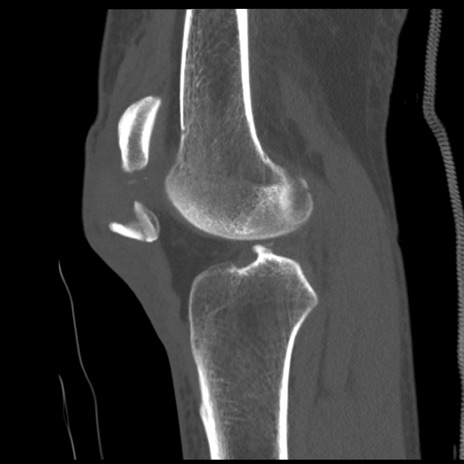

症例28 右膝関節CT(矢状断像)

右膝関節CT